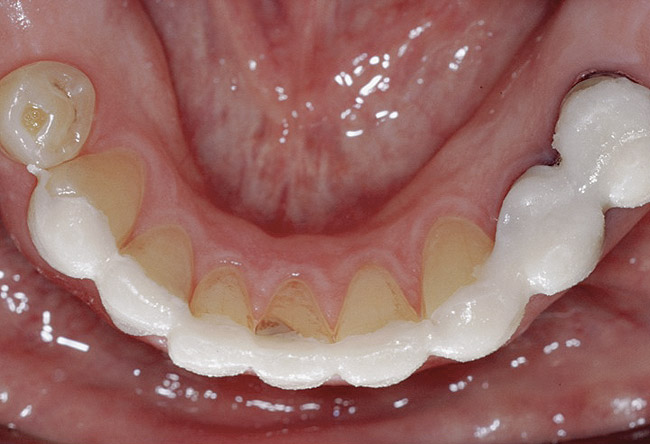

Figure 16 THROUGH 19. Complete full mouth wax-ups after final determination of 3D VDO.

Diagnostic Wax-Ups and Set-Ups

One of the most valuable ways to assess vertical dimension is to use wax-ups to create mock overlays to test clear speech for an appropriate vertical dimension (Figure 14 and Figure 15). When anterior diagnostic acrylic or composite overlays (or “mock veneers”) are used to test fricatives, clear [f] and [v] sounds are made when the incisal edges of the maxillary teeth touch just inside the wet/dry border of the lower lip. Clear sibilant [s] and [z] sounds occur when the lower and upper incisal edges almost touch, allowing a clear hissing sound to be made. Improved esthetics is also dramatic. Once these sounds are clear, the closest speaking space can be created with diagnostic wax-ups in the posterior space (Figure 16 through Figure 19). The final result will depend on successful development of 3D VDO comparing a number of methodologies.